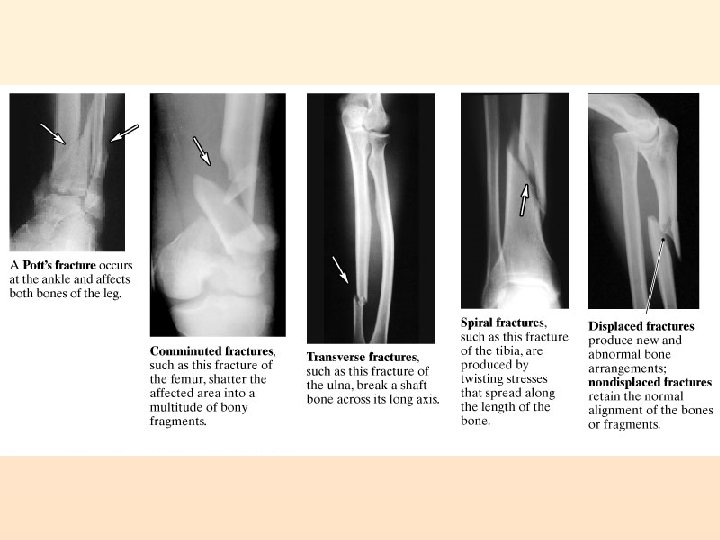

Fractures Simple (Closed): Compound (Open):